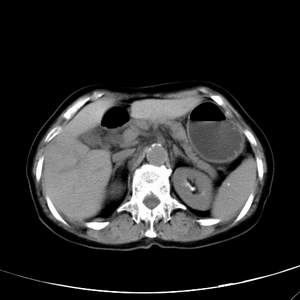

患者,女性,77岁,右上腹胀痛月余。afp正常。ca125升高。即往无肝炎病史。

肝右叶病灶是胆管细胞癌吗?门静脉右支癌栓形成?右侧肾上腺有问题吗?

最后5幅图片是延时7分钟的。门静脉右前支内有充缺吗?如有,肝血管瘤不好解释。

渐进性强化,中间见沙砾样钙化,首先考虑血管瘤

病灶渐进性向心性强化,延时病灶中心见条片状高密度影,局部见肝包膜回缩征,结合病人无肝炎病史,考虑肝右叶胆管细胞癌,门脉右支癌栓形成。